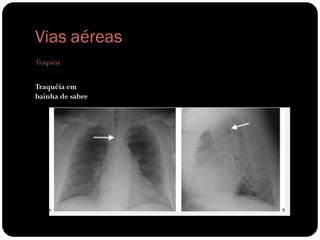

Vias aéreas

Traquéia

Traquéia em

bainha de sabre

Diâmetro coronal

menos que 2/3 do

diâmetro sagital

DPOC

Transmissão crônica

do aumento da

pressão intrapleural

E lesão por tosse

crônica;